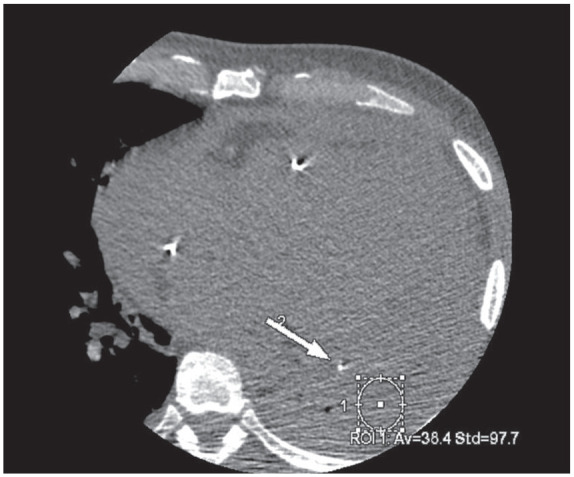

假性动脉瘤是心肌梗死(MI)的一种罕见但致命的并发症。随着心血管疾病检测和治疗技术的进步,心肌梗死后致命的结构性并发症现在已经很少见了。一旦发生,先进的诊断方法可用于早期诊断,帮助制定手术计划并改善预后。在我们的病例中,心脏计算机断层扫描血管造影术(CCTA)诊断出了心肌梗死后左心室假性动脉瘤并发血心包。CCTA 的衰减测量有助于诊断血心包的活动性外渗。该病例强调了对心肌梗死后罕见但致命的并发症需要高度怀疑,以及 CCTA 在治疗中的作用。

Pseudoaneurysm is a rare but fatal complication of myocardial infarction (MI). With the advances in cardiovascular disease detection and treatments, fatal structural complications post-MI are now rare. When they occur, advanced diagnostic modalities can be used for early diagnosis, aiding surgical planning, and improving prognosis. In our case, post-MI left ventricle pseudoaneurysm complicated by hemopericardium was diagnosed using cardiac computed tomography angiography (CCTA). Use of attenuation measurement on CCTA helped diagnose active extravasation into the hemopericardium. This case highlights the high index of suspicion needed for rare but fatal complications post-MI and the utility of CCTA in their management.